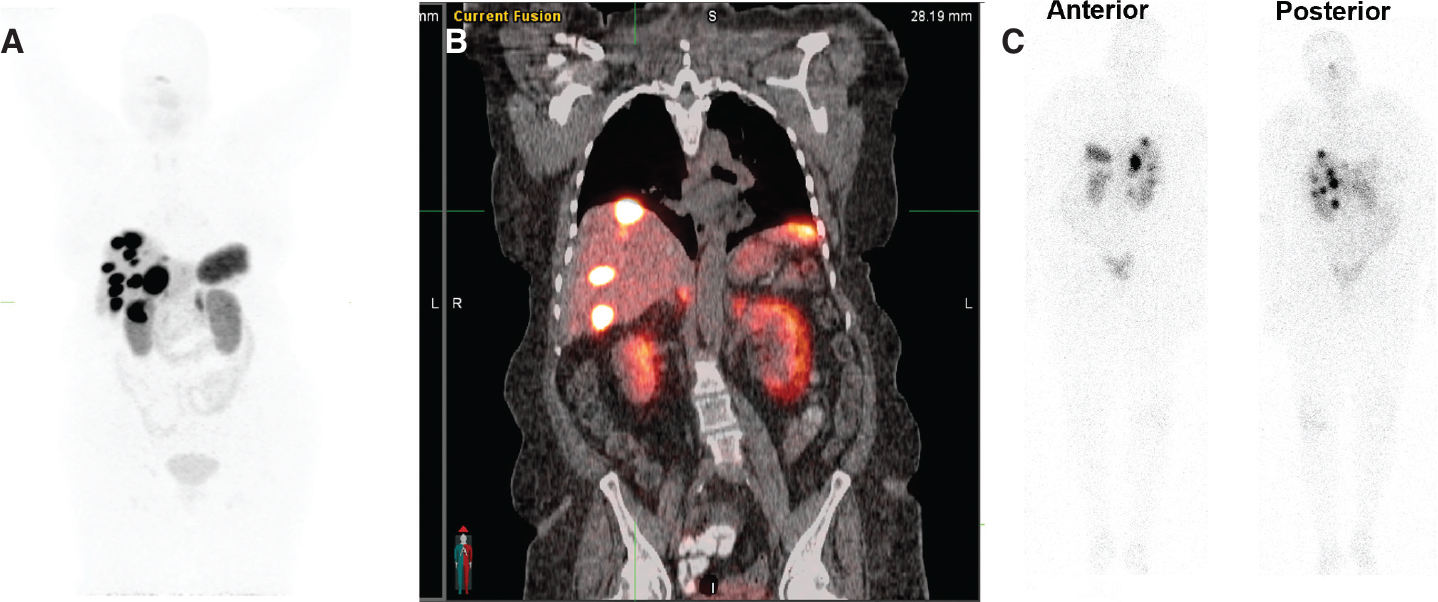

Patients are evaluated by a multidisciplinary NET team, including a medical oncologist, an oncological surgeon, and a nuclear medicine physician (who must be an authorized user) to decide on the appropriateness and timing of PRRT in individual patients. Ideal candidates for PRRT include patients with well-differentiated and moderately-differentiated neuroendocrine carcinomas defined as NET grade 1 or 2 according to the recent WHO 2010 classification (39). Patients considered for PRRT should undergo diagnostic somatostatin receptor imaging such as SSTR PET scan or SSTR scintigraphy (111In-pentetreotide) to demonstrate adequate SSTR expression (40) (Figure 4). The two FDA approved SSTR positron emission tomography (PET) imaging agents are Gallium-68 (68Ga) DOTATATE and Copper-64 (64Cu) DOTATATE. These diagnostic imaging agents constitute diagnostic components of PRRT Theranostics.

Fig 4

Figure 4. A 74-year-old female with advanced and inoperable metastatic ileal NET. A. 68Ga-DOTATATE (SSTR PET) MIP image and B. Fused coronal image show multiple intensely somatostatin receptor-rich tumors in the liver and portocaval lymph node.